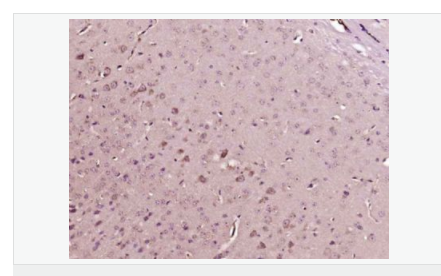

交叉反應(yīng):Human,Mouse,Rat(predicted:Phosphotyrosine) 推薦應(yīng)用:IHC-P,IHC-F,ICC,IF

| 產(chǎn)品應(yīng)用 | IHC-P=1:100-500 IHC-F=1:100-500 ICC=1:100-500 IF=1:100-500 (石蠟切片需做抗原修復(fù)) not yet tested in other applications. optimal dilutions/concentrations should be determined by the end user. |

| 產(chǎn)品介紹 | The phosphorylation of specific tyrosine residues has been shown to be a primary mechanism of signal transduction during normal mitogenesis, cell cycle progression and oncogenic transformation, its role in other areas such as differentiation and gap junction communication, is a matter of active and ongoing research. Antibodies that specifically recognize phosphorylated tyrosine residues have proved to be invaluable to the study of tyrosine phosphorylated proteins and the biochemical pathways in which they function. SWISS: N/A CAS: 21820-51-9 Important Note: This product as supplied is intended for research use only, not for use in human, therapeutic or diagnostic applications. |